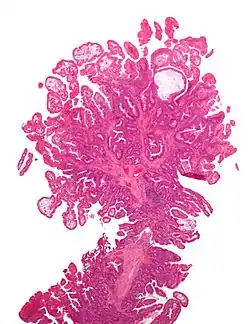

![]() صورة ميكروسكوبية لسليلة قولونية من نوع بوتز-جيغرز صورة ميكروسكوبية لسليلة قولونية من نوع بوتز-جيغرز | |